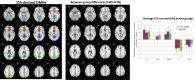

The brain's default mode network (DMN) is highly heritable and is compromised in a variety of psychiatric disorders. However, genetic control over the DMN in schizophrenia (SZ) and psychotic bipolar disorder (PBP) is largely unknown. Study subjects (n = 1,305) underwent a resting-state functional MRI scan and were analyzed by a two-stage approach. The initial analysis used independent component analysis (ICA) in 324 healthy controls, 296 SZ probands, 300 PBP probands, 179 unaffected first-degree relatives of SZ probands (SZREL), and 206 unaffected first-degree relatives of PBP probands to identify DMNs and to test their biomarker and/or endophenotype status. A subset of controls and probands (n = 549) then was subjected to a parallel ICA (para-ICA) to identify imaging-genetic relationships. ICA identified three DMNs. Hypo-connectivity was observed in both patient groups in all DMNs. Similar patterns observed in SZREL were restricted to only one network. DMN connectivity also correlated with several symptom measures. Para-ICA identified five sub-DMNs that were significantly associated with five different genetic networks. Several top-ranking SNPs across these networks belonged to previously identified, well-known psychosis/mood disorder genes. Global enrichment analyses revealed processes including NMDA-related long-term potentiation, PKA, immune response signaling, axon guidance, and synaptogenesis that significantly influenced DMN modulation in psychoses. In summary, we observed both unique and shared impairments in functional connectivity across the SZ and PBP cohorts; these impairments were selectively familial only for SZREL. Genes regulating specific neurodevelopment/transmission processes primarily mediated DMN disconnectivity. The study thus identifies biological pathways related to a widely researched quantitative trait that might suggest novel, targeted drug treatments for these diseases.